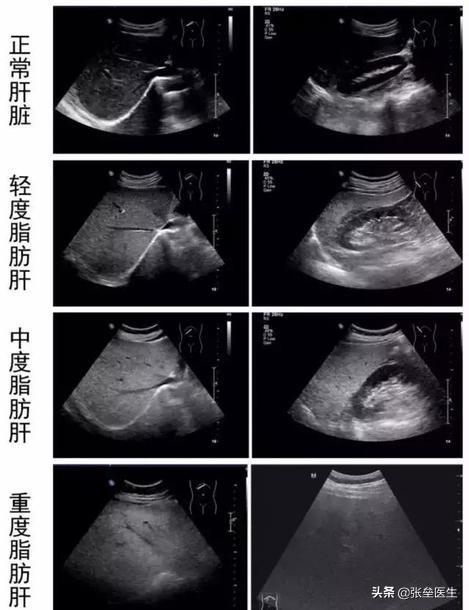

● Certains d'entre vous se demanderont peut-être comment faire pour distinguer s'il s'agit d'une stéatose hépatique légère ou sévère ou grave ? En fait, comme je l'ai mentionné dans le paragraphe d'introduction, il s'agit d'une constatation rapportée sur l'imagerie qui...Il y a donc plus de subjectivité.D'une manière généraleS'il est douxL'échographie comprend une stéatose hépatique inhomogène. Le foie est de taille normale avec une forte échogénicité parenchymateuse, le champ postérieur est clair et les structures canalaires sont montrées et amincies ;si modéréA l'échographie, le volume hépatique est important, l'angle marginal hépatique est émoussé, les échos parenchymateux sont finement rehaussés avec une légère atténuation dans le champ postérieur, les structures tubulaires sont peu visibles et amincies, et il y a un contraste important entre le foie et les reins.Dans les cas graves, le foie présente une morphologie pleine et une taille nettement augmentée à l'échographie, avec des angles marginaux hépatiques arrondis, des échos parenchymateux finement renforcés sous forme de nuages, une atténuation dans les champs moyen et postérieur, des structures tubulaires peu visibles et une augmentation du contraste entre le foie et les reins.